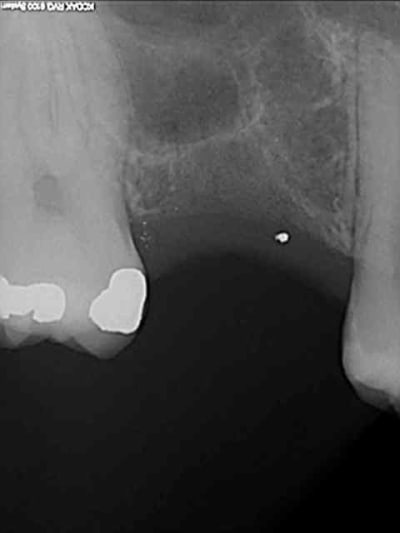

je sais pas si c'est un produit miracle, mais pour les sinus lift, c'est fantastique.

outre le fait de stabiliser un implant dans un sinus type SA4, pas de risque de voir partir le produit comme avec les granules de bioos et autres..

l'autre avantage est de ne pas avoir à mettre de membrane de recouvrement.

je suis donc hyper satisfait du résultat.

jugez plutôt...

une toute petite remarque, le point blanc sur la radio avec pilier de cicatrisation.

tu as raison, mais on le voit dés les premières radios post extraction.

j'en déduis donc que j'ai bossé comme un cochon pendant cet acte et qu'une inclusion (amalgame ?) est restée dans la gencive.